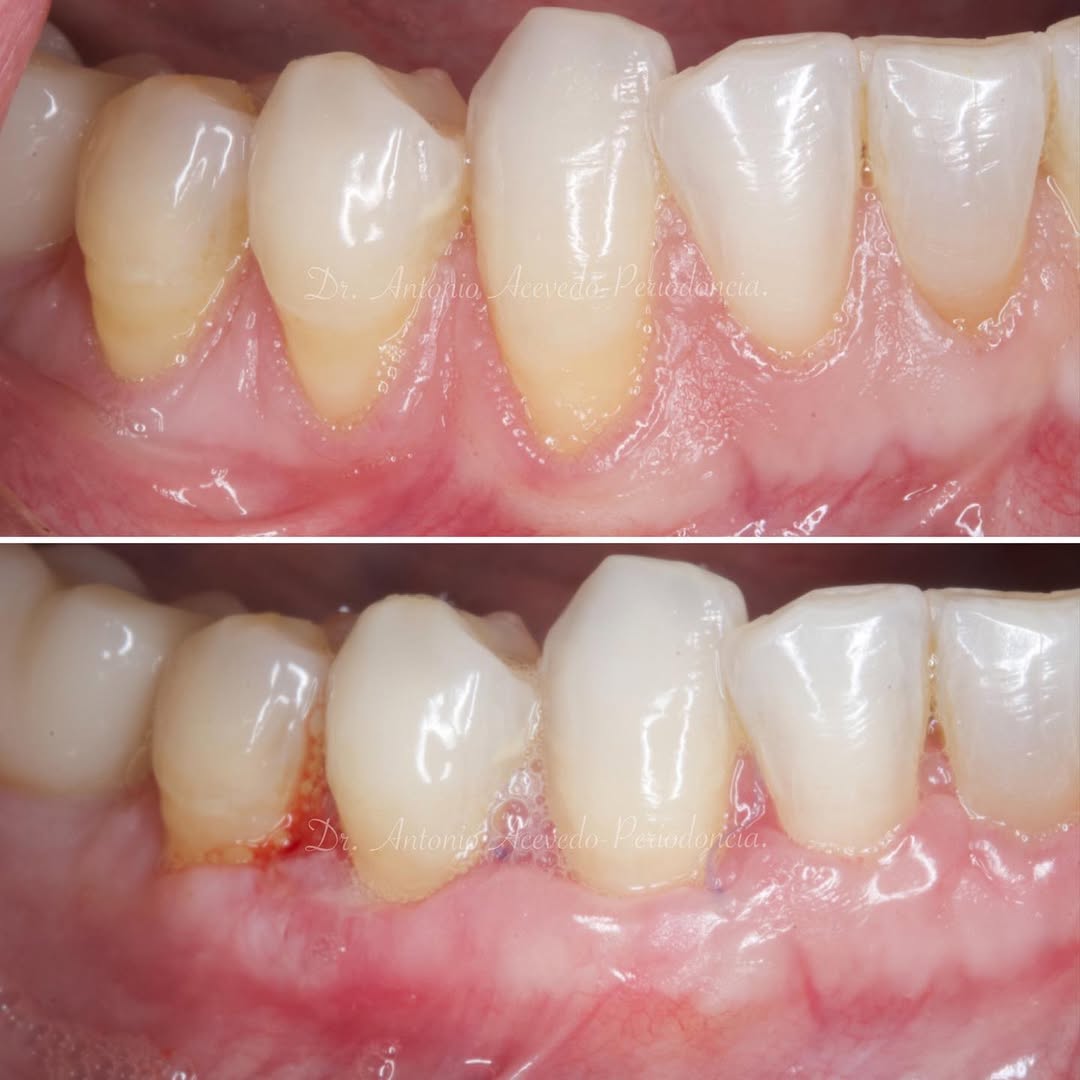

Durante una mañana, asistirás a una Cirugía Mucogingival de recubrimiento radicular de recesiones múltiples en IV y V sextante (36 a 43).

Gracias al uso del microscopio y a la proyección en tiempo real en pantalla, verás exactamente lo mismo que veo yo durante la cirugía, sin tener que estar

Podrás asistir a la planificación de casos y cirugía de injerto de tejido conectivo. Factores determinantes y elección de la técnica adecuada. Sumérgete en un protocolo predecible y técnicamente correcto para obtener resultados óptimos.

Aprende la planificación y técnica de la cirugía Mucogingival para el recubrimiento de recesiones y aumento de banda queratinizada en el sector anteroinferior

Una estancia clínica pensada para quienes quieran iniciarse o dar un paso más en el campo de la cirugía mucogingival. Durante esta experiencia tendrás la oportunidad de aprender en directo cómo se planifica y se lleva a cabo una cirugía mucogingival mediante técnica de Túnel.

La sesión